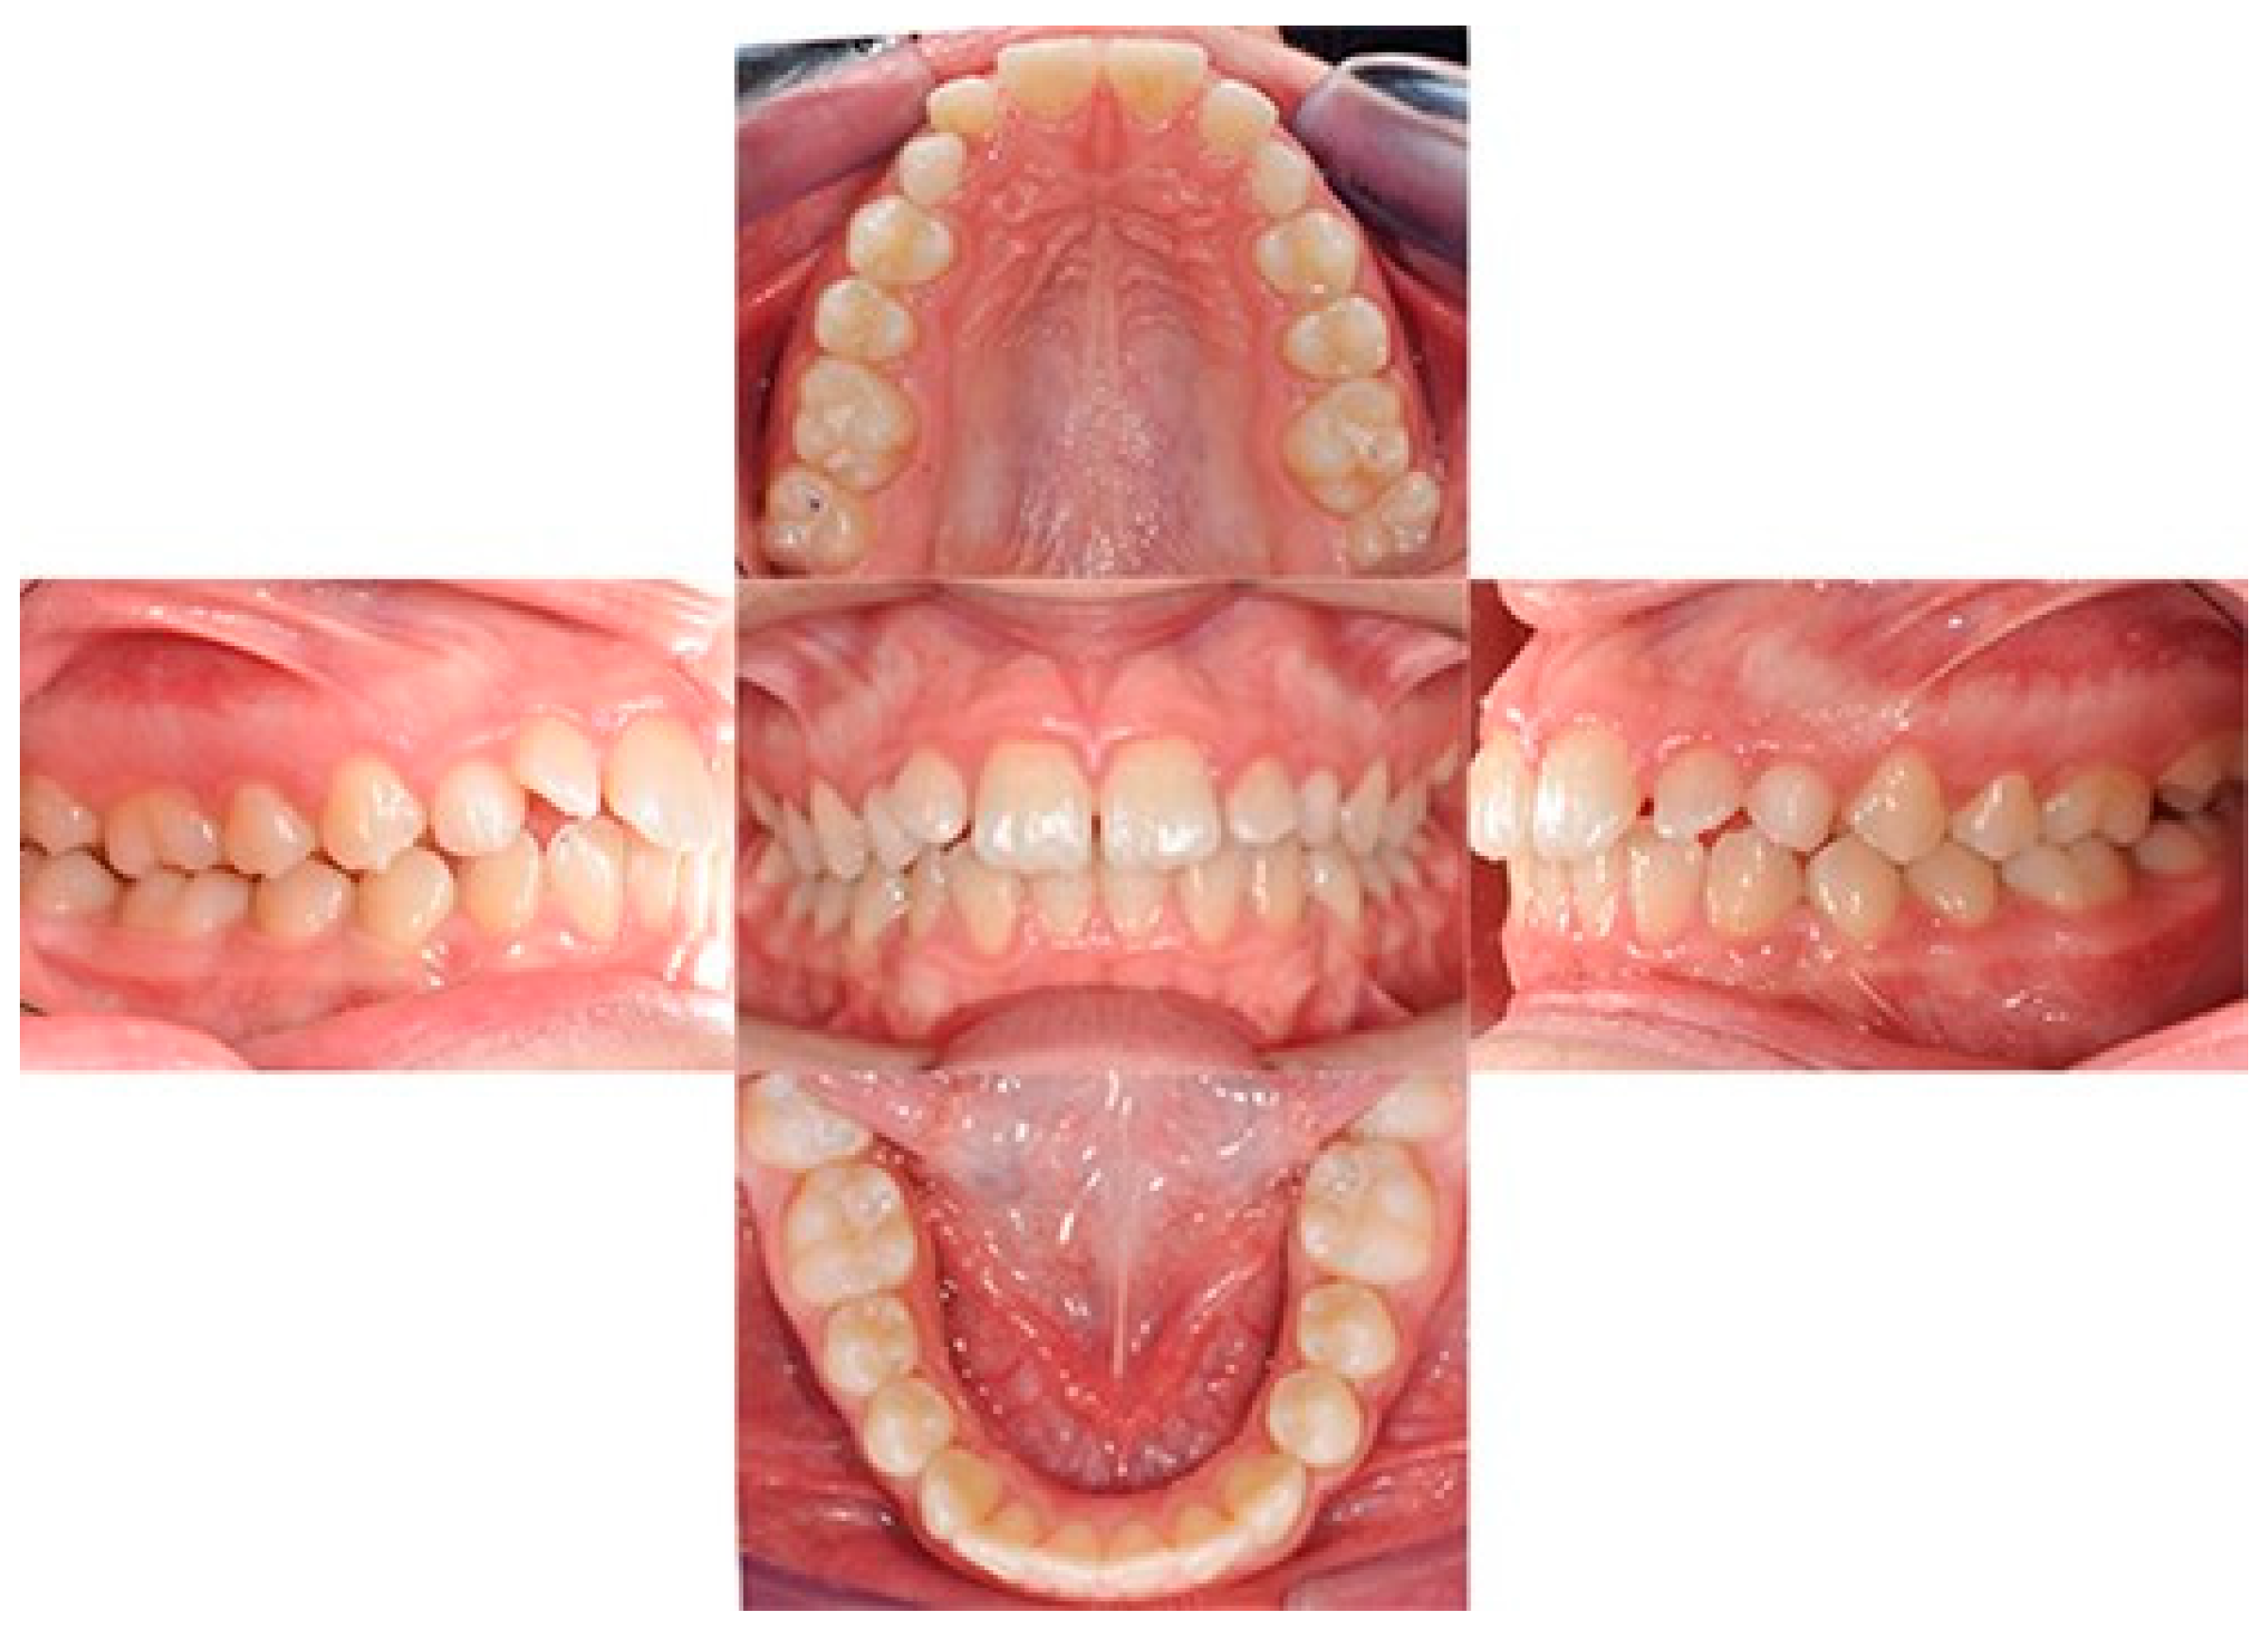

A 12-year-old girl with the second skeletal class (ANB 5), a high angle (FMA 27), and a facial index of 0.67 was selected. Soft tissue analysis showed a convex profile with a Z angle equal to 57 and an FMIA angle close to 55. The IMPA angle was 98. The analysis of the dental cast revealed a spee curve of 3.5 mm (Table 1). The occlusion presented a first molar class to the left, and a light second class to the right with 1 mm crowding in the lower jaw. The overjet was 0. The upper canines were impacted (Figure 1, Figure 2 and Figure 3). The patient’s chief complaint was altered aesthetic perception due to reduced dimensions of the deciduous canines. The treatment objectives were to retrieve space for upper canines’ eruption, level the spee curve, upright the lower incisors, and reduce the impact of the convex profile through occlusal vertical control to facilitate counterclockwise mandibular rotation.

Figure 1. Initial intraoral photos.